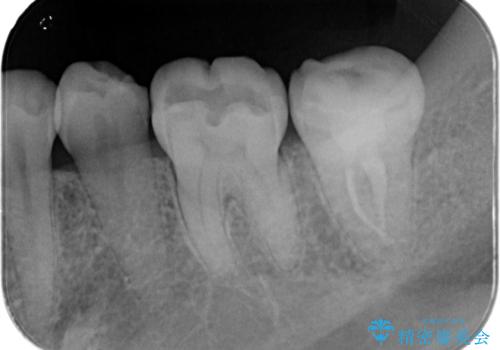

【根管治療・オールセラミッククラウン】何もしなくても歯が痛い 咬むと更に痛い

上下の歯が接触するだけで痛い 根管治療とオールセラミック治療

【精密根管治療】奥歯がズキズキ痛い。